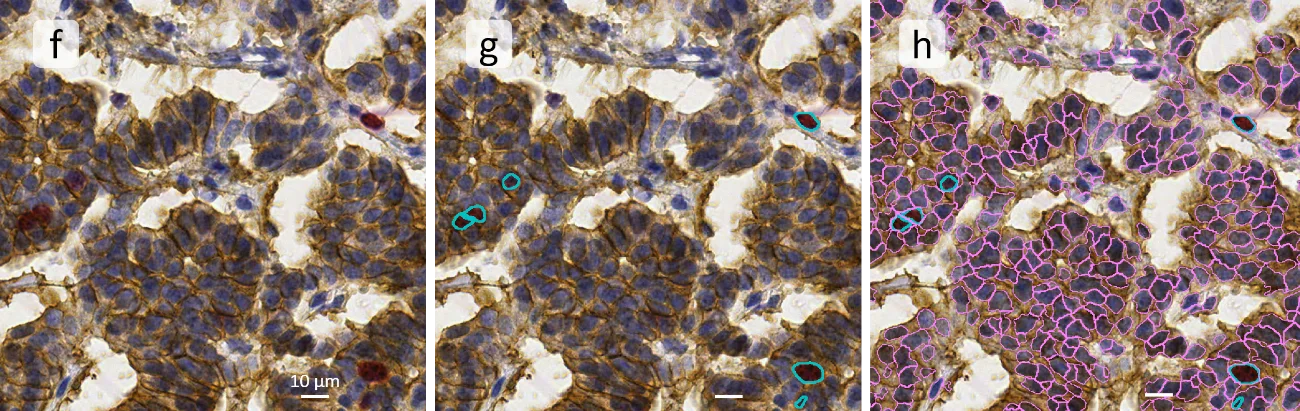

Next, these channels are used as the basis for cell segmentation (nuclei) and marker detection (Ki67, NCAM): (f) is the original image, (g) shows Ki67+ cells in turquoise nuclei mask, and (h) combined overall cell detection in pink, with Ki67+ cells highlighted in turquoise.